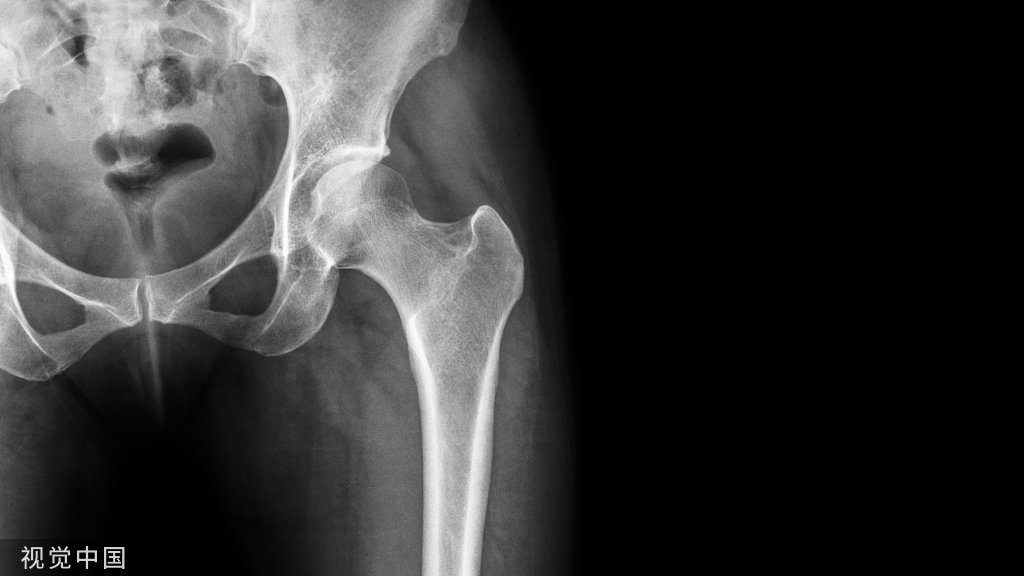

进针点:S1、2骶孔之间外1/3。S1椎弓根钉进针点显露后,继续向尾端显露出骨嵴,S2AI进针点就在嵴上,和S1椎弓根钉在一条线。不必显露骶孔,容易出血、损伤神经。

另外可以通过L5、S1椎弓根钉的间距判断S2AI钉大概位置范围。这几个钉子的间距差不多一样,也在一条线上。